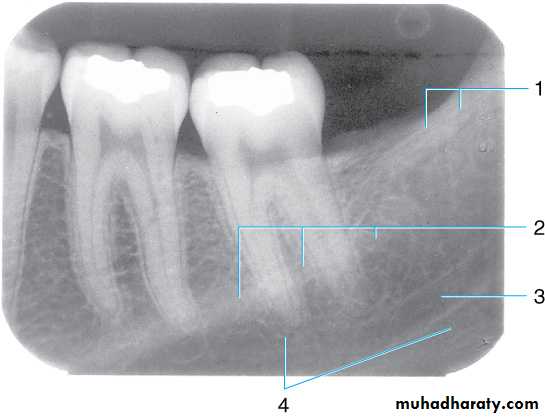

Bitewing radiograph. This radiograph shows (1) large occlusal caries, (2) radiolucent lines or mach band effect (an optical illusion caused by overlapped enamel), (3) interproximal caries, and

(4) cervical burnout